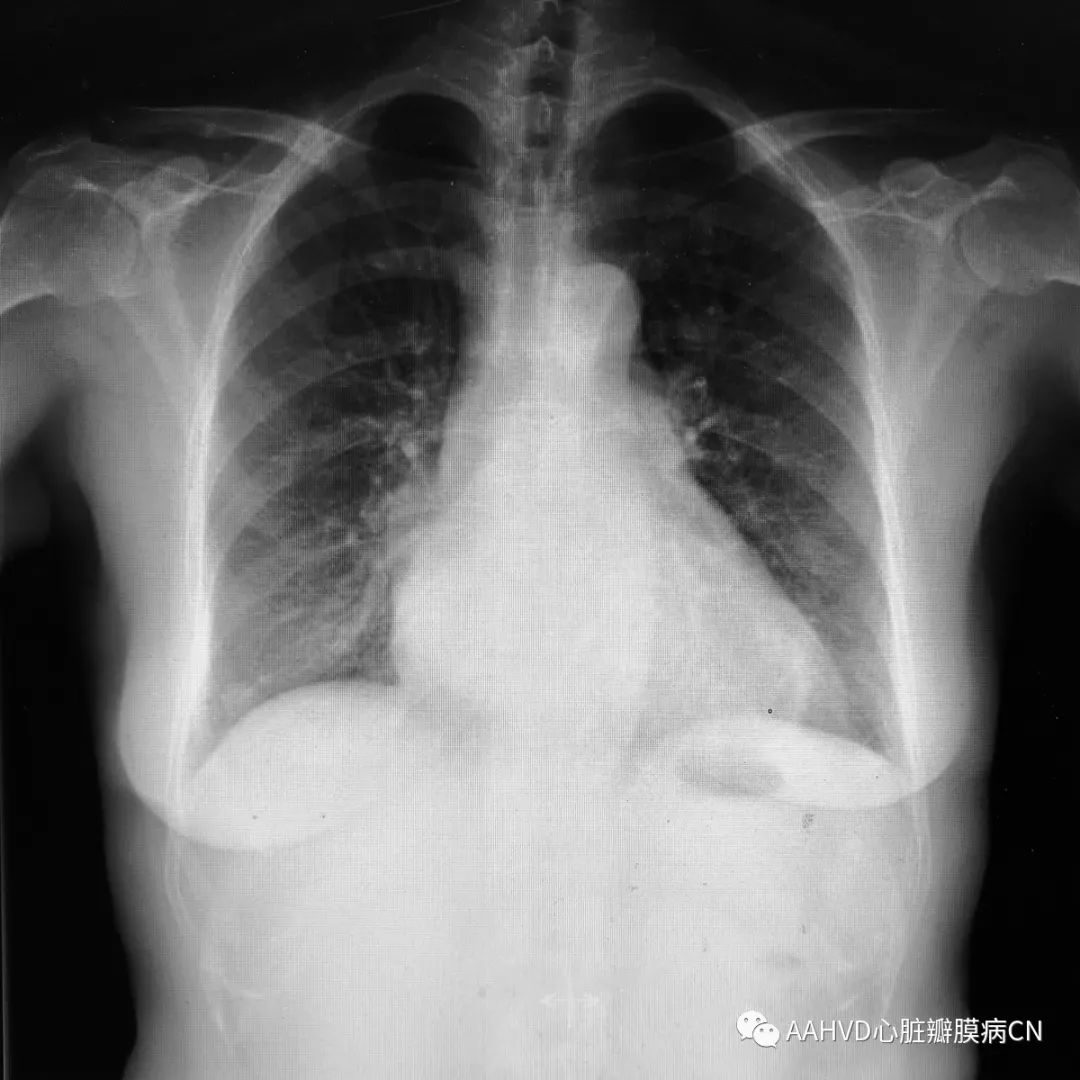

术前胸片

640_7

男性,63岁,主诉:胸闷憋气一周

手术日期:2018年12月24日

术前经胸超声:

风湿性瓣膜病改变不除外,二尖瓣返流面积12.7cm²(重度返流),瓣口面积1.9cm²(轻度狭窄),E前向流速296cm/s;三尖瓣返流面积7.5cm²(中量返流)。